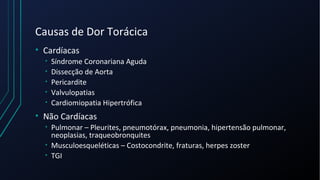

Dor torácica pode ter diversas causas, incluindo cardíacas como síndrome coronariana aguda, dissecção de aorta e pericardite, e não cardíacas como problemas pulmonares, musculoesqueléticos e do trato gastrointestinal. É importante avaliar a história clínica, características da dor e exame físico para identificar a possível causa e orientar o tratamento adequado.